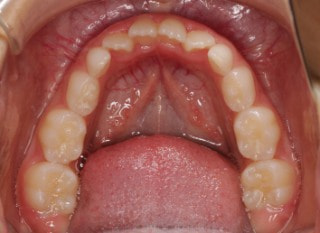

小児期の第二段階

終了時